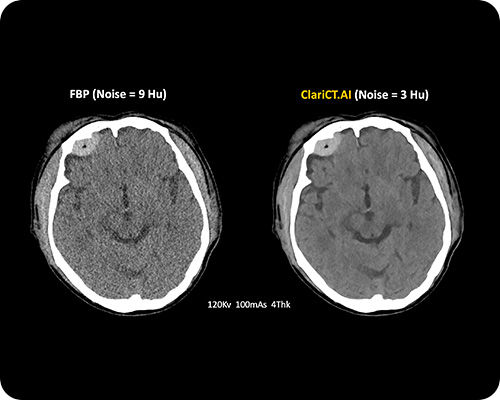

ClariCT.AI

AI-Powered Radiation Reduction

The first AI software that dramatically reduces radiation exposure while delivering the highest quality CT images using advanced AI denoising technology.

Reduces radiation exposure by 70-95% while maintaining superior image quality